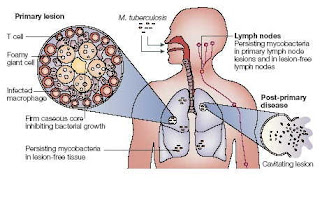

รูปที่11

: Tuberculous meningitis

สาเหตุ : เยื่อหุ้มสมองอักเสบจากวัณโรค (Tuberculous meningitis) เกิดจากเชื้อวัณโรค

ซึ่งมักจะแพร่กระจายจากปอด หรือส่วนอื่น ๆ

ของร่างกายมาที่เยื่อหุ้มสมองโดยผ่านทางกระแสเลือด โรคนี้มักจะมีอาการค่อย ๆ

เกิดขึ้นอย่างช้า ๆ อาจกินเวลาเป็นสัปดาห์

แต่ผู้ป่วยมักจะมาหาหมอเมื่อมีอาการรุนแรง จึงทำให้มีอัตราตาย

หรือพิการค่อนข้างสูง พบได้ทั้งในเด็กและผู้ใหญ่ พบมากในเด็กอายุ 1-5 ปี